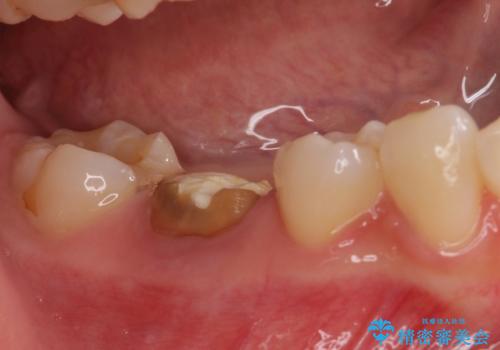

- セラミッククラウンが破損したため、職場近くのクリニックで治療開始したものの、当院への転院を希望して来院された患者様です。

クラウン再製作の際、提案された根管治療を開始したものの、処置の度に痛みを感じるとのことでした。

当院にて根管治療を行った後に、フルジルコニアクラウンにて補綴することとしました。

前医での根管治療の度に感じていた痛みの原因は分かりませんでしたが、元々違和感すらなかった歯であったので、速やかに根管治療を行った後に、ジルコニアクラウンを装着しました。